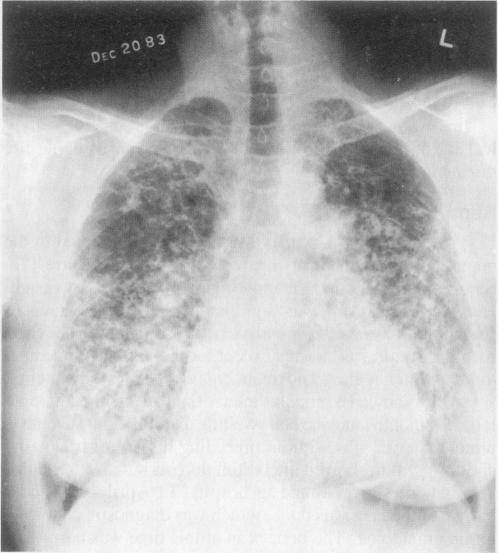

Multifocal eosinophilic granuloma with a pituitary stalk lesion.

West J Med. 1985 Jun;142(6):829-31.

Multifocal eosinophilic granuloma with a pituitary stalk lesion.伴有垂体柄病变的多灶性嗜酸性肉芽肿